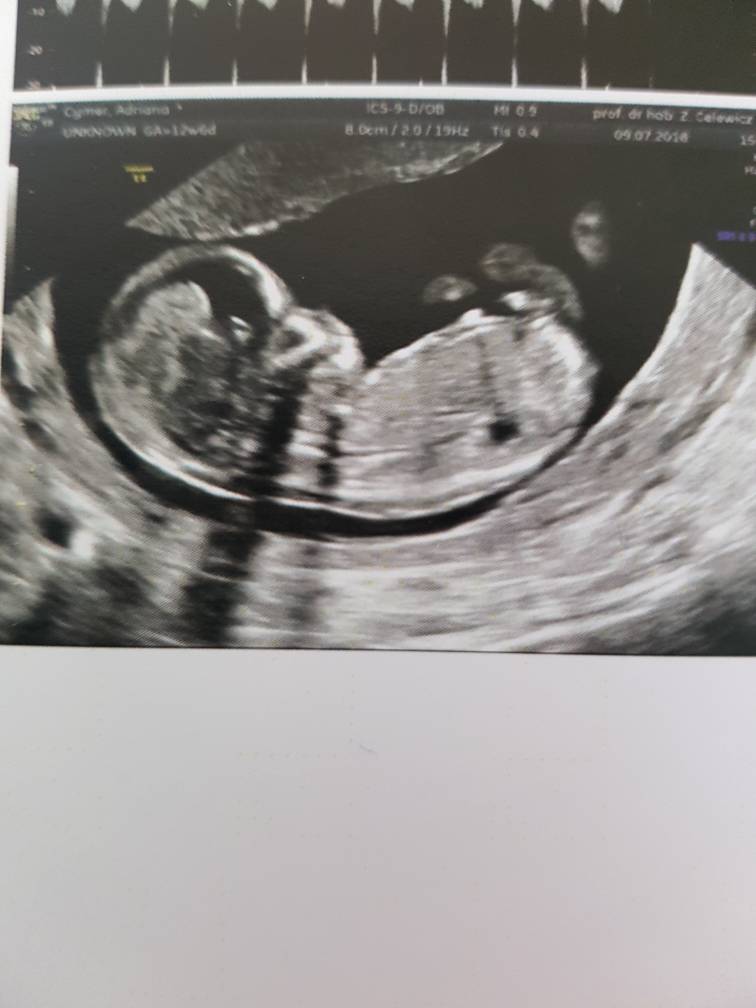

Mam 6.51cm taki już duży jestem :-)

Pięknie machałem do mamy i taty i ładnie współpracowałem z Panią doktor :-)

Pani doktor powiedziała, że wyglądam jej na chłopca i by się bardzo zdziwiła jeśli okazałoby się, że jestem dziewczynką ;) także jak na razie zostaję Mateuszkiem[emoji170] [emoji7] Co mamie się zgadza bo tak czuje[emoji12]

na USG wszystko w porządku, jeszcze tylko trzeba poczekać na wyniki z krwi ale mama jest dobrej myśli :)